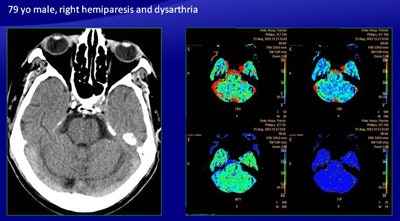

There were discordant results with automatically generated perfusion maps in the case of a 79-year-old man presenting with right hemiparesis and dysarthria (above). Manual mapping showed an area of reduced CBV, reduced CBF, and increased MTT in the left pons, suggesting infarction of the pons, but the color map showed only abnormalities, leading to a false negative as confirmed on follow-up CT (below).

There were discordant results with automatically generated perfusion maps in the case of a 79-year-old man presenting with right hemiparesis and dysarthria (above). Manual mapping showed an area of reduced CBV, reduced CBF, and increased MTT in the left pons, suggesting infarction of the pons, but the color map showed only abnormalities, leading to a false negative as confirmed on follow-up CT (below).For infarcted tissue, in four of 14 cases there was a discordance -- all true positive on the manually generated maps and all false positive on the software generated maps. These included three false positives in the basal ganglia. There was also one false negative produced by the software.

"There was an area of reduced CBV, reduced CBF, and increased MTT in the left pons, suggesting an infarction of the pons, but the color map showed only abnormalities, leading to a false negative revealed in the follow-up CT, which showed a large infarct in the pons," Ukmar said.